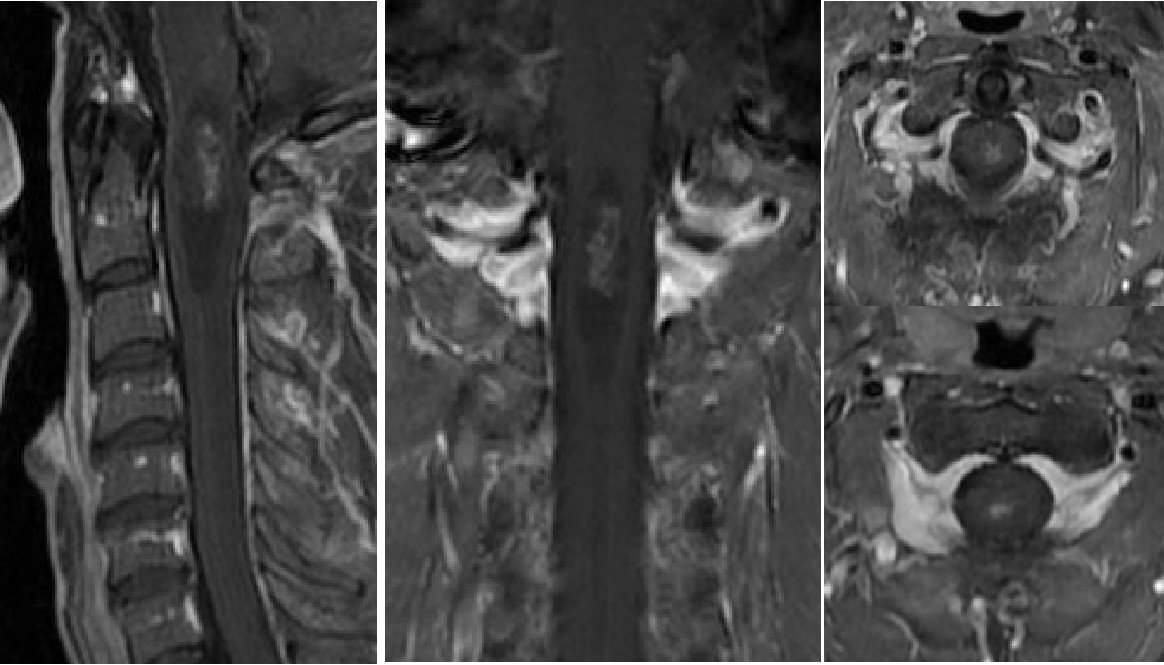

图3 张先生在我院复查的核磁,病变范围从延髓到颈3椎体上缘

据王贵怀主任介绍,张先生罹患的是一种脊髓髓内肿瘤,很多病人长时间都没有明确症状,有些人会有“颈椎病”类似的表现。从患者目前的影像检查和病史来判读,考虑是室管膜瘤,它是脊髓常见的髓内肿瘤,这种病药物无法治愈,只能通过手术治疗,如果能够做到全切,术中对正常神经充分保护的话,病人将开启下一段正常的人生。但是肿瘤位置特殊,长在延髓到颈3椎体水平的脊髓内,手术需要切开脊髓进行,稍有不慎就会导致病人瘫痪,甚至呼吸心跳骤停,手术风险和难度极大。

图4 患者术后复查磁共振提示肿瘤全切